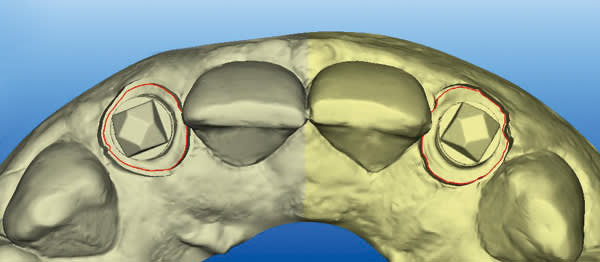

An intraoral digital impression of both custom scan bodies No. 7 and No. 10 was made with the itero digital impression system to create an STL file (Figure 17 and Figure 18). The custom shape of the scan bodies is clearly seen with red line margins in both the facial and occlusal views shown in Figure 19 and Figure 20.

The STL files were downloaded into the design program, creating a virtual working cast. The virtual cast illustrates the red margin line created by the custom scan body transfer, which will guide the laboratory in the designing of the definitive abutment margins (Figure 21). In addition, the STL files were utilized to fabricate a master cast created by CAD/CAM modeling of urethane material. The completed abutment design shows a dotted blue line depicting the margin line created from the custom scan body transfer (Figure 22). The virtual abutments’ STL files were then uploaded to the design software for CAD/CAM fabrication of the definitive zirconia abutments. After the abutments were received back at the laboratory, they were placed on the master cast, evaluated/modified (Figure 23), and scanned into prosthesis design software. The definitive prostheses were fabricated with zirconia copings and layered porcelain.